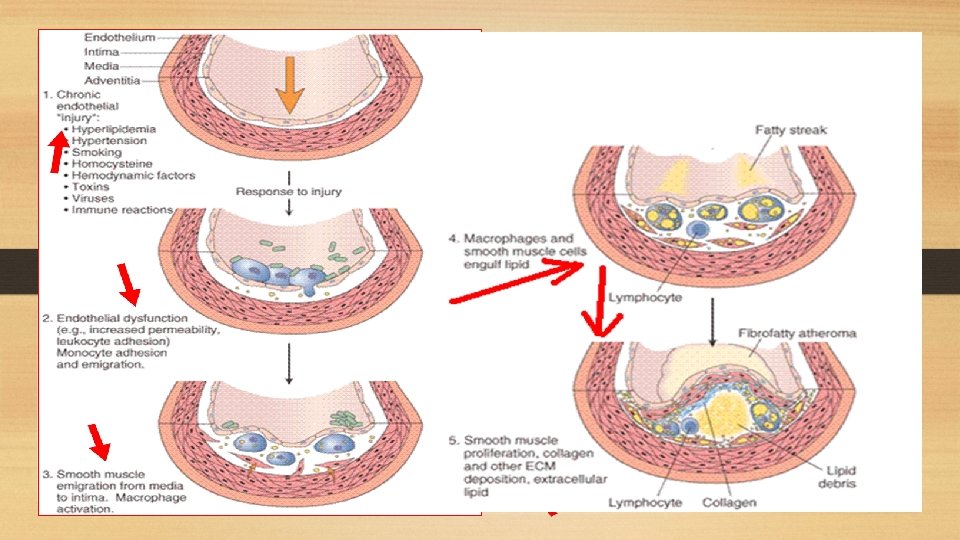

Pathogenesis of Atherosclerosis: i. Endothelial injury: - Is the initial triggering event in the development of lesions of atherosclerosis. - Risk factors such as hypertension, cigarette smoking and chronic hyperlipidemia can cause endothelial damage. ii. Role of blood monocytes: - Plasma LDL on entry into the injured intima undergoes oxidation. - The 'oxidized LDL' performs the following functions on monocytes and endothelium: a. For monocytes, oxidized LDL acts to attract, proliferate, immobilize and activate them to transform it to a lipid-laden foam cell after LDL engulfment. Death of foam cell by apoptosis releases lipid to form lipid core of plaque. b. For endothelium, oxidized LDL is cytotoxic. iii. Smooth muscle cell proliferation: - Endothelial injury causes adherence, aggregation and platelet release reaction at the site of exposed subendothelial connective tissue. - Migration of smooth muscles from media to intima occurs first, followed by Proliferation of smooth muscle cells which is stimulated by various mitogens, the most important of which is platelet-derived growth factor (PDGF).

Pathologic changes: A. Fatty streaks and dots: - The atherosclerotic process occurs gradually within long duration (begins in young age) and starts with formation of what is called fatty streaks and dots on the intima. - By themselves, fatty streaks and dots are harmless but may be the precursor lesions of atheromatous plaques. Gross picture: - The lesions may appear as flat or slightly elevated and yellow. - They may be either in the form of small, multiple dots, about 1 mm in size, or in the form of elongated, beaded streaks. Microscopic picture: - Fatty streaks lying under the endothelium are composed of closely-packed foam cells, lipid-containing elongated smooth muscle cells and a few lymphoid cells. - Small amount of extracellular lipid, collagen and proteoglycans are also present.

B. Atheromatous plaques: - Is a fully developed atherosclerotic lesion, also called fibrous plaque, fibrofatty plaque or atheroma. - Most affected is the abdominal aorta, however it may be seen in descending thoracic aorta and aortic arch. Gross picture: -Are white to yellowish-white lesions, varying in diameter from 1 -2 cm and raised on the surface. - Cut section of the plaque reveals the luminal surface as a firm, white fibrous cap and a central core composed of yellow to yellow-white, soft material.